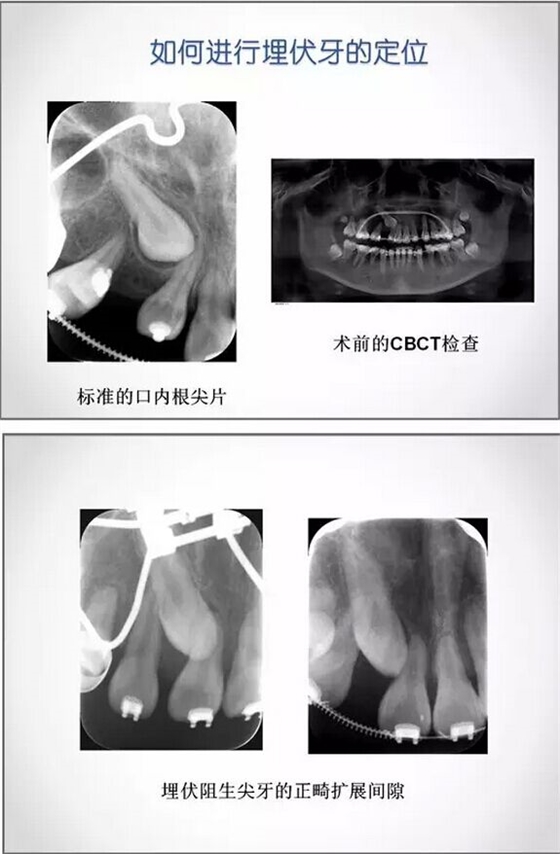

埋伏牙正畸治療中的外科開窗術(shù)